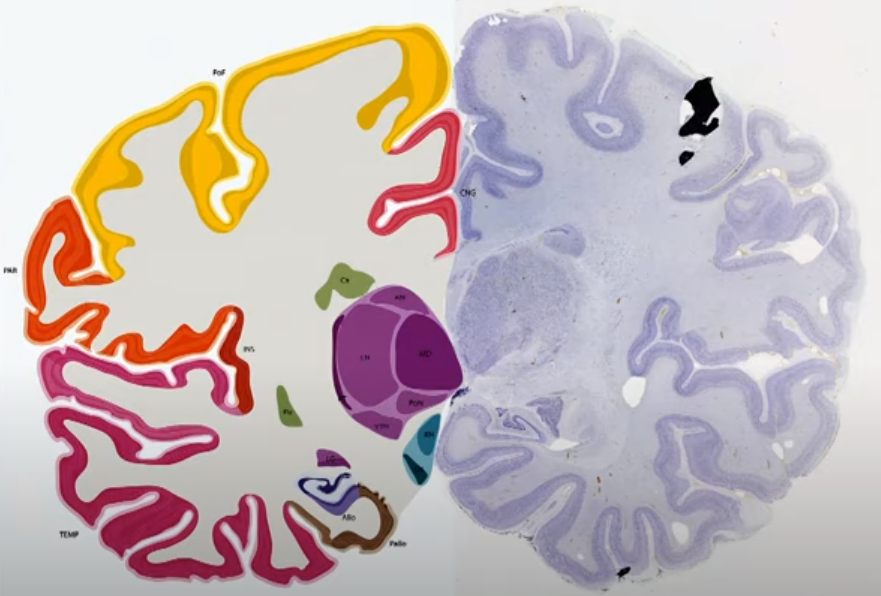

专家根据被染色的细胞聚集的情况找到组织的边界,作为随后定位和分割的解剖参考

最后将基因表达的数据map到MRI的空间中